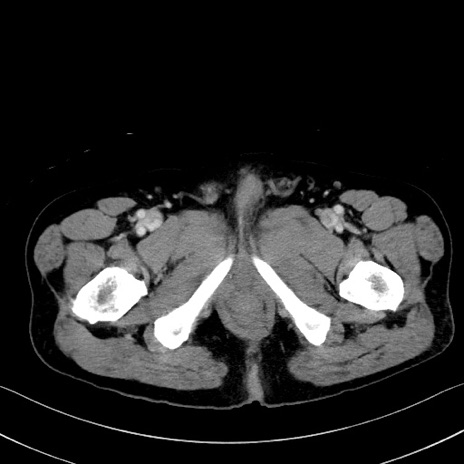

冠状断像

【症例】70歳代 男性

【主訴】腹部膨満、嘔吐

【現病歴】昨日より腹部膨満感出現。本日増悪し、仙痛出現。嘔吐あり、受診。

【既往歴】糖尿病、胆摘後

【身体所見】BP 149/80mmHg、HR 74/min、BT 35.9℃、腹部:膨満、軟、圧痛なし。腸雑音減弱あり。上腹部正中切開瘢痕あり。

【データ】WBC 13500、CRP 1.72